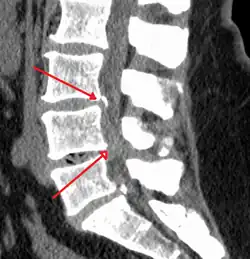

Spinal stenosis is an abnormal narrowing of the spinal canal or neural foramen that results in pressure on the spinal cord or nerve roots.[6] Symptoms may include pain, numbness, or weakness in the arms or legs.[1] Symptoms are typically gradual in onset and improve with leaning forward.[1] Severe symptoms may include loss of bladder control, loss of bowel control, or sexual dysfunction.[1]

Causes may include osteoarthritis, rheumatoid arthritis, spinal tumors, trauma, Paget's disease of the bone, scoliosis, spondylolisthesis, and the genetic condition achondroplasia.[3] It can be classified by the part of the spine affected into cervical, thoracic, and lumbar stenosis.[2] Lumbar stenosis is the most common, followed by cervical stenosis.[2] Diagnosis is generally based on symptoms and medical imaging.[4]

The diagnosis of spinal stenosis involves a complete evaluation of the spine. The process usually begins with a medical history and physical examination. X-ray and MRI scans are typically used to determine the extent and location of the nerve compression.